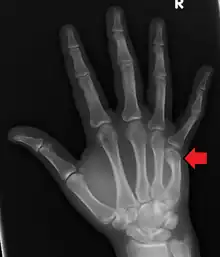

Boxer's fracture of the 5th metacarpal head from punching a wall

A boxer's fracture is the break of the metacarpal bone of the hand near the knuckle at the base of the little finger.[2] Occasionally it is used to refer to fractures of the 4th metacarpal as well.[1] Symptoms include pain and a depressed knuckle.[3]

Classically, it occurs after a person hits an object with a closed fist.[2] The knuckle is then bent towards the palm of the hand.[4] Diagnosis is generally suspected based on symptoms and confirmed with X-rays.[4]

Diagnosis by a doctor’s examination is the most common, often confirmed by x-rays. X-ray is used to display the fracture and the angulations of the fracture. A CT scan may be done in very rare cases to provide a more detailed picture.[8]